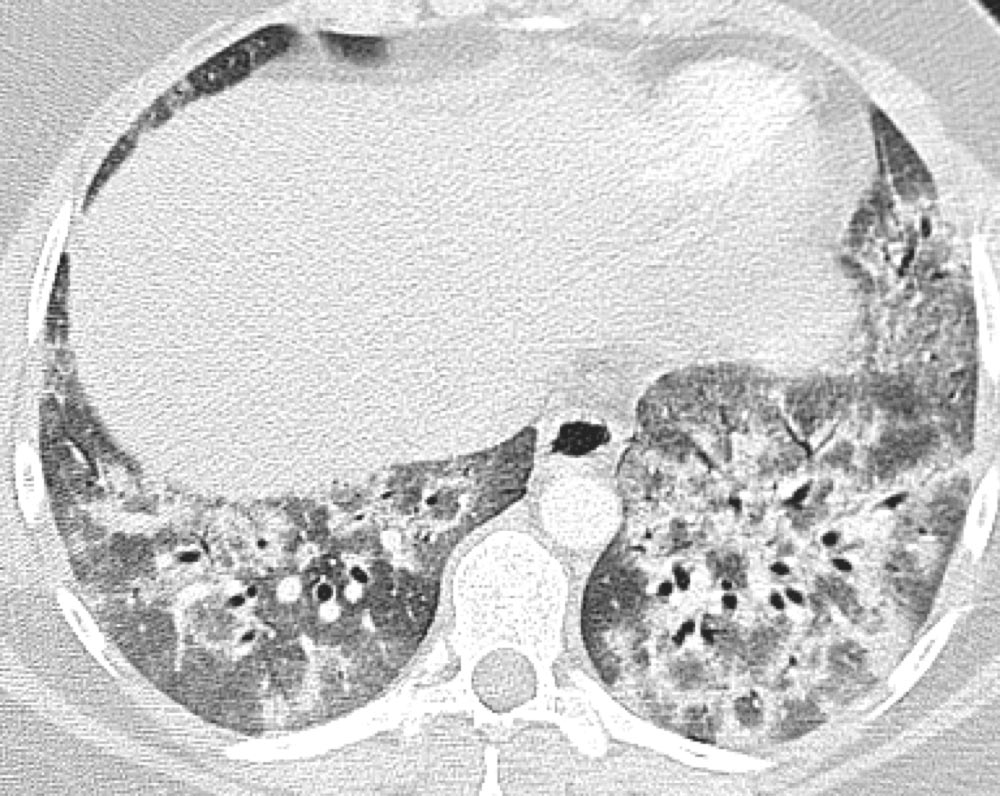

Axial HRCT showing significant honeycombing in a predominantly subpleural pattern at the bases of the lung with peripheral reticulation and traction bronchiectasis. Note the asymmetric pattern of fibrosis, a hallmark feature of usual interstitial pneumonia (UIP).

Image courtesy of and used with permission from Sudhakar Pipavath, MD.